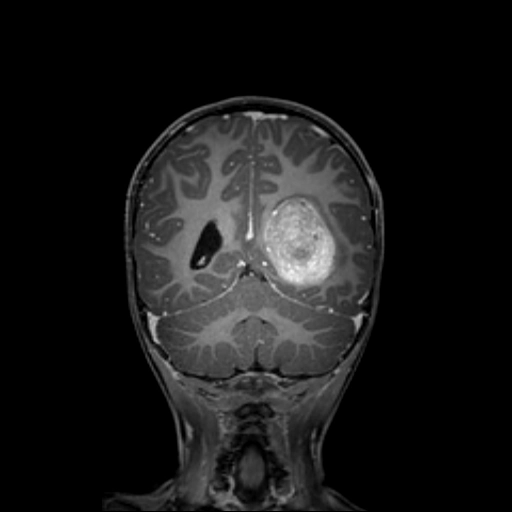

• U đám rối mạch mạc (Choroid Plexus Tumors)

• Ung thư biểu mô đám rối mạch mạc (Choroid Plexus Carcinoma)